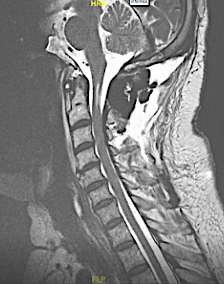

RM postoperatoria: sólo se extirparon los schwannomas C2 que causaban clínica compresiva

Corte axial en C2 postoperatorio